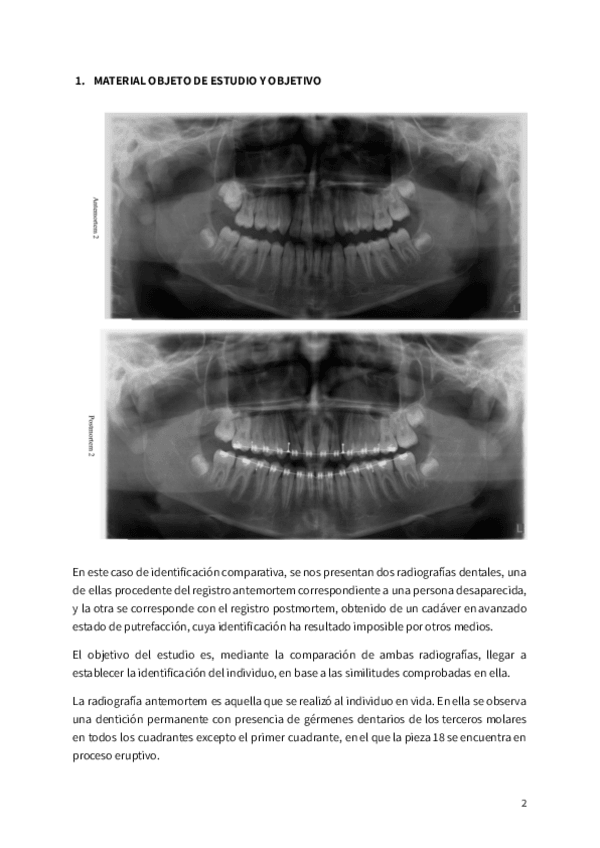

PRACTICA-3-Identificacion-comparativa.pdf